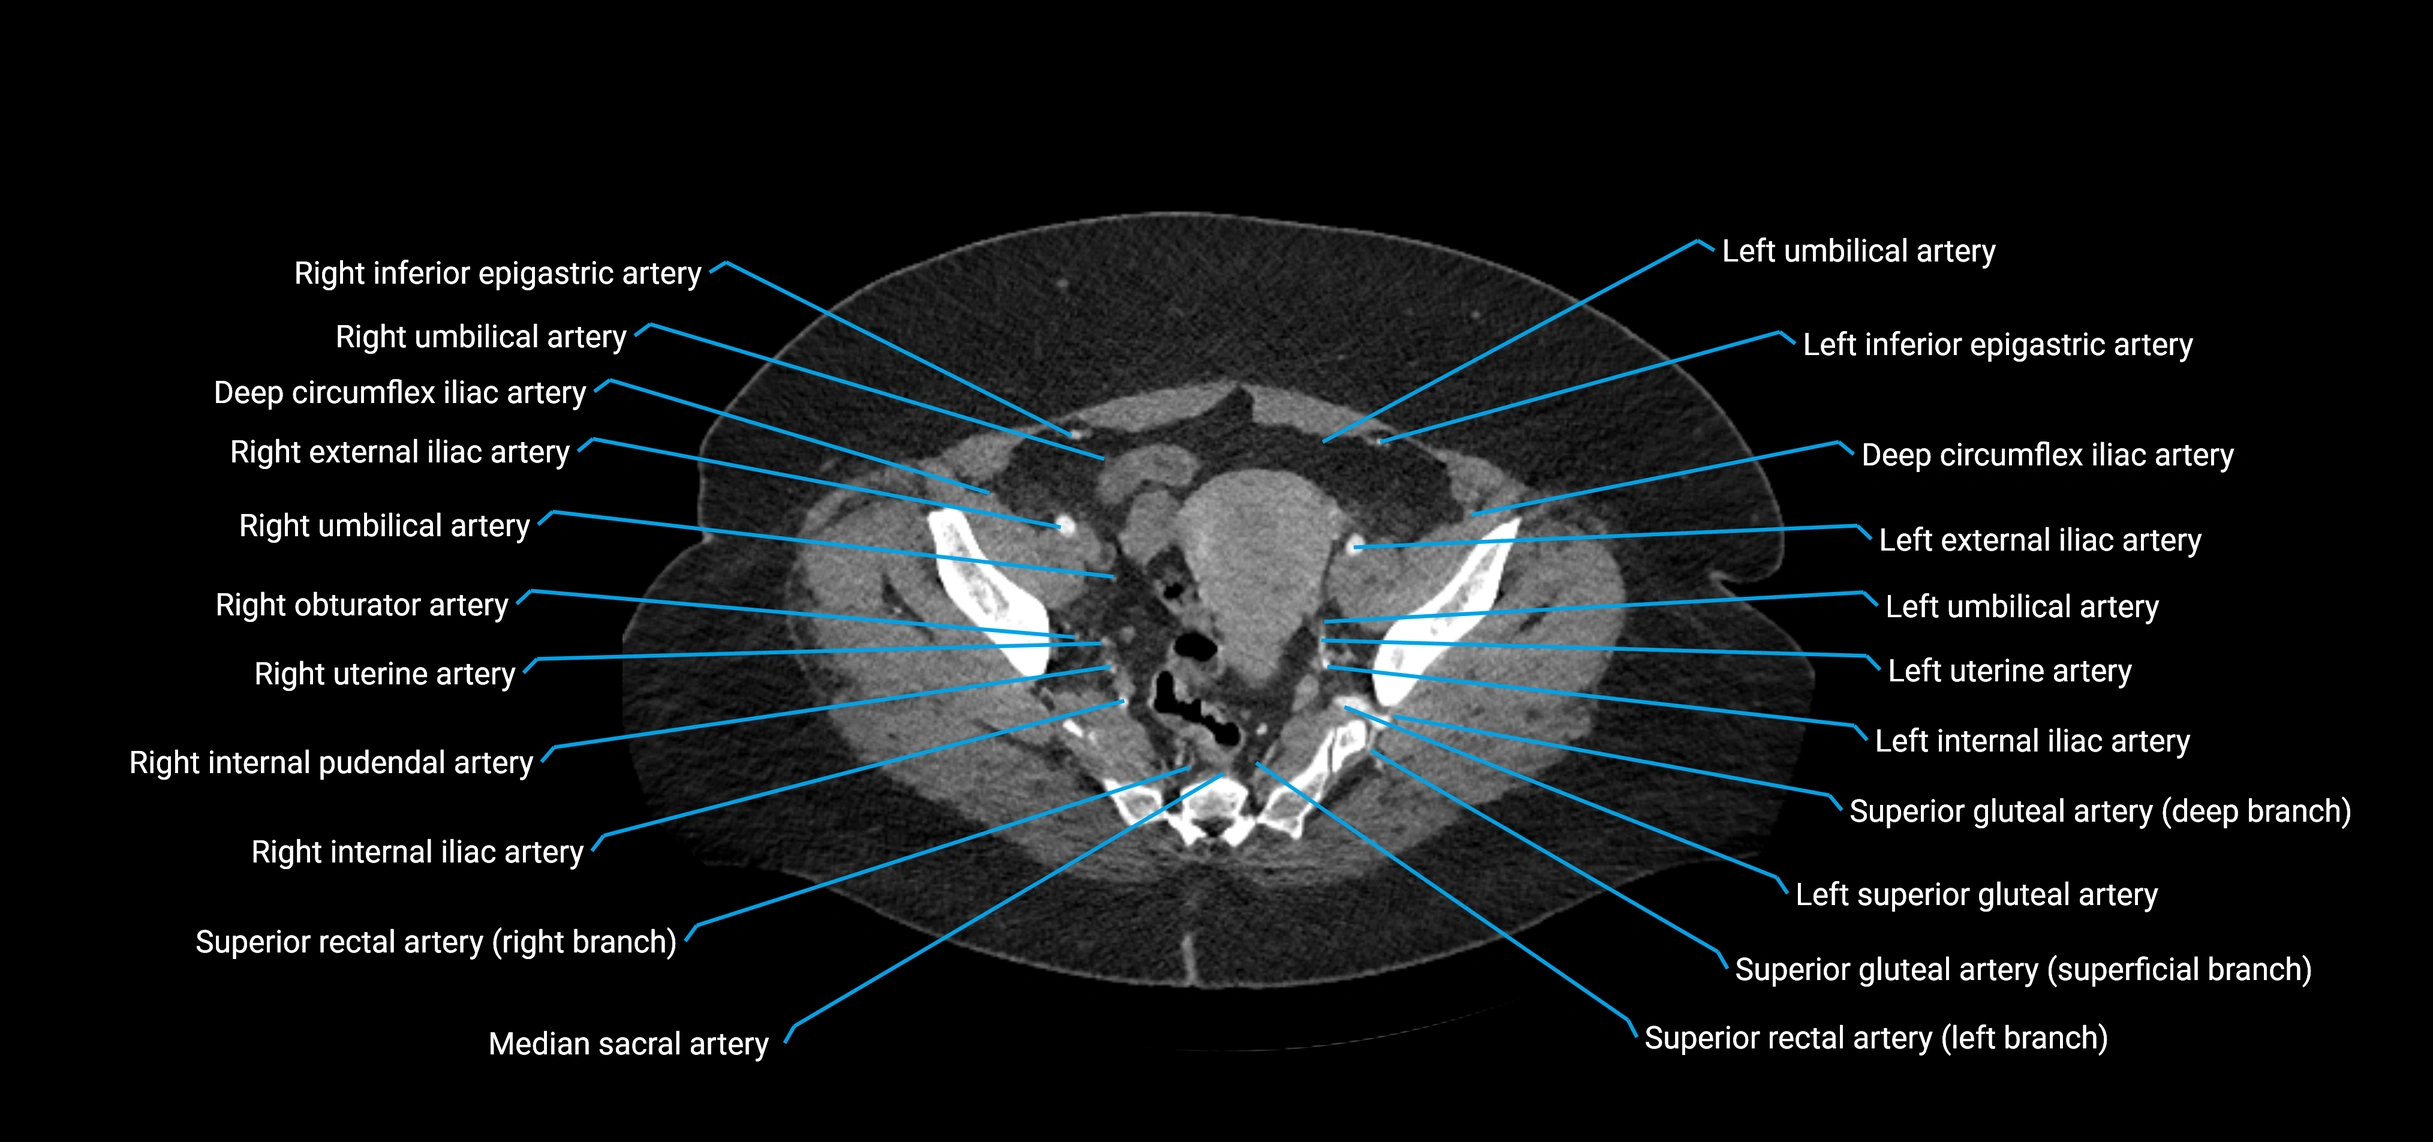

CT images

image

Contrast-enhanced CT (CTA):

• Gold standard for abdominal aortic imaging

• Provides excellent detail of lumen, wall, aneurysm, thrombus, and branch vessels

• Multiplanar and 3D reconstructions help in aneurysm measurement, stent graft planning, and dissection evaluation

• Detects acute rupture, traumatic injury, or occlusion with high sensitivity